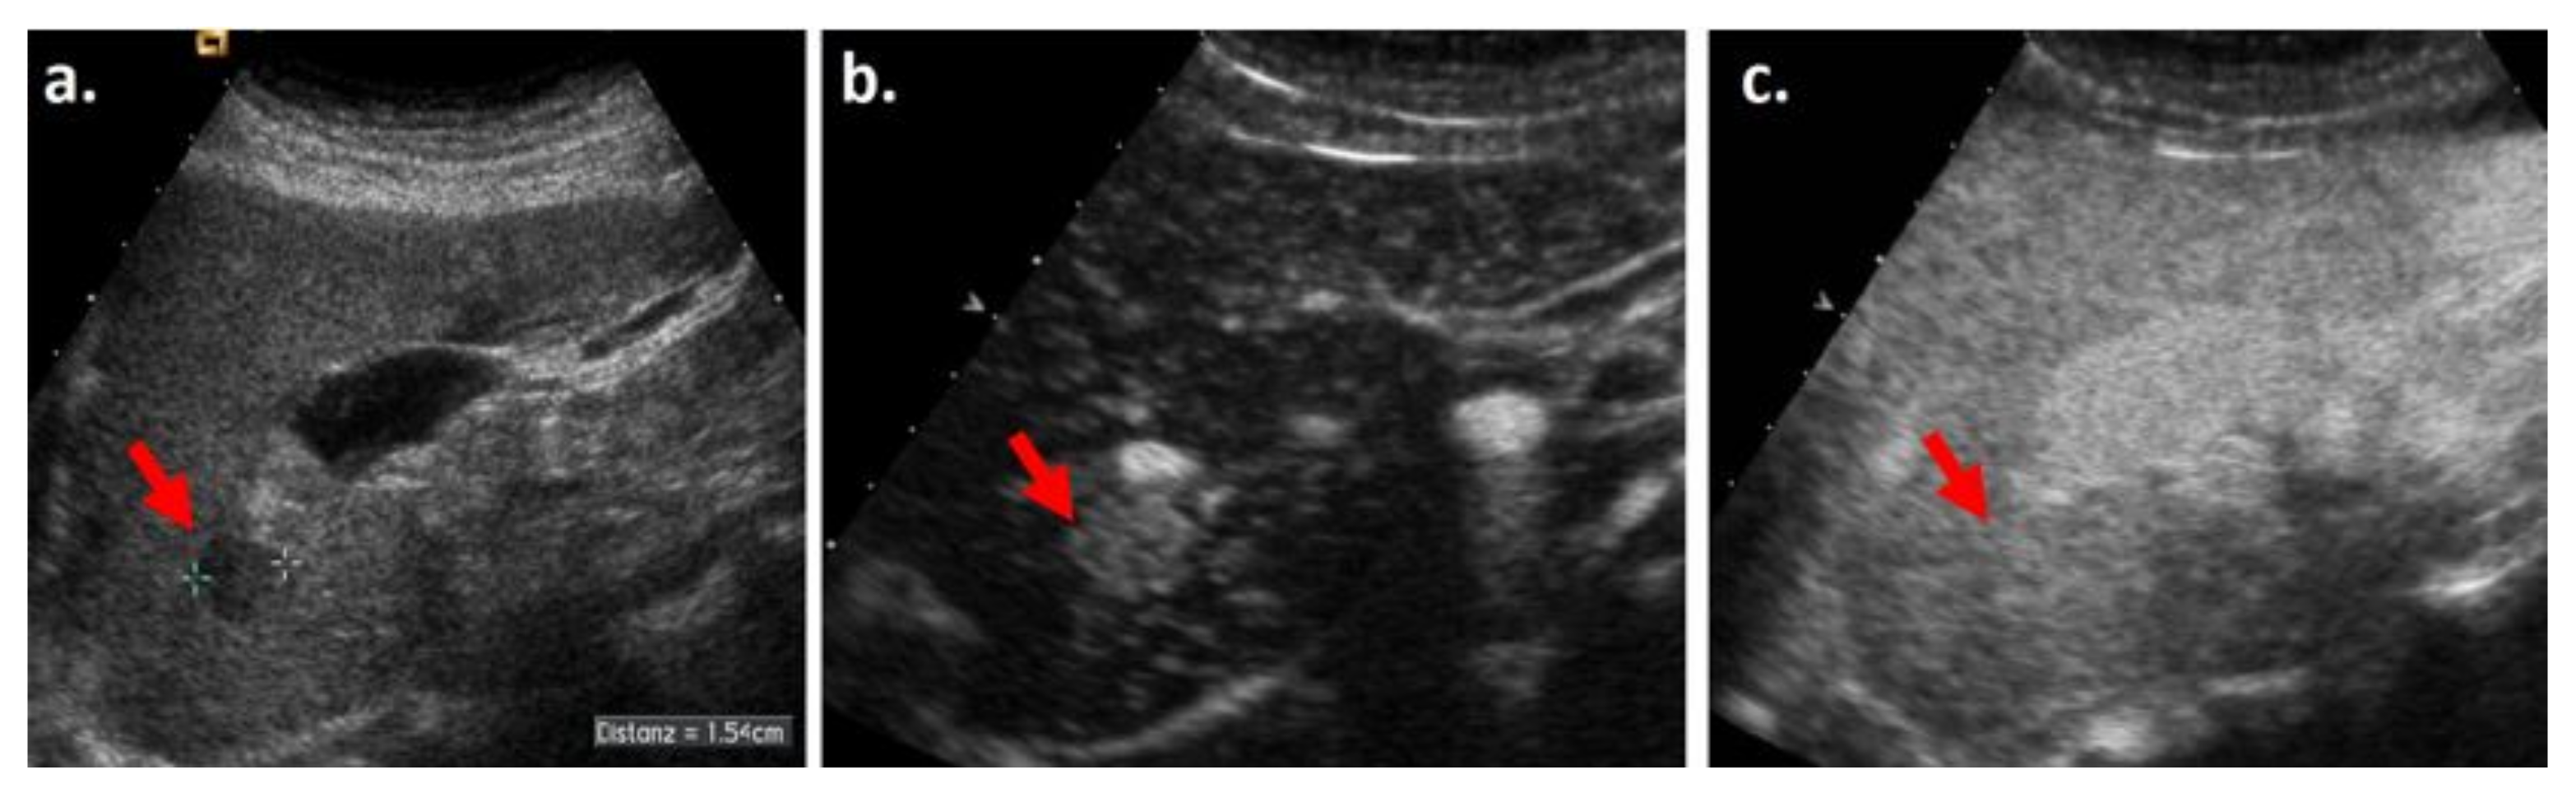

3.1. Arterial Phase Hyperenhacement (APHE)

3.1.1. Definition

3.1.2. Comparison of CEUS, CECT, and MRI, Similarities and Differences

Similarities

Differences and Complementarity of Techniques